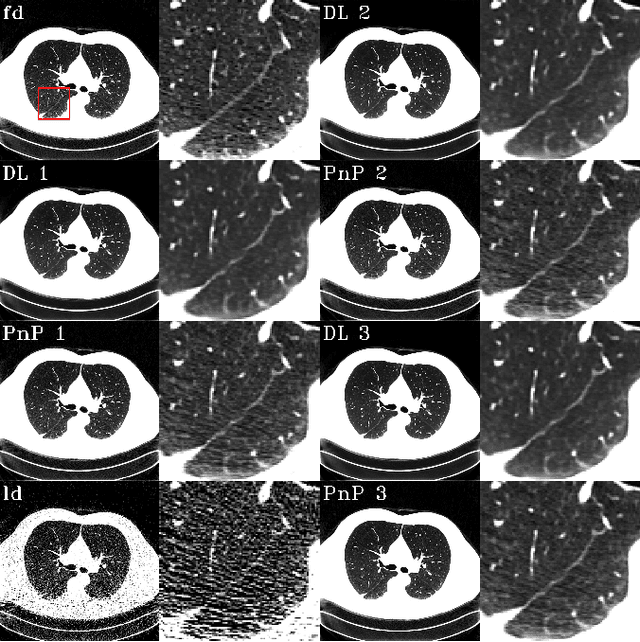

Abstract:The Plug-and-Play (PnP) framework was recently introduced for low-dose CT reconstruction to leverage the interpretability and the flexibility of model-based methods to incorporate various plugins, such as trained deep learning (DL) neural networks. However, the benefits of PnP vs. state-of-the-art DL methods have not been clearly demonstrated. In this work, we proposed an improved PnP framework to address the previous limitations and develop clinical-relevant segmentation metrics for quantitative result assessment. Compared with the DL alone methods, our proposed PnP framework was slightly inferior in MSE and PSNR. However, the power spectrum of the resulting images better matched that of full-dose images than that of DL denoised images. The resulting images supported higher accuracy in airway segmentation than DL denoised images for all the ten patients in the test set, more substantially on the airways with a cross-section smaller than 0.61cm$^2$, and outperformed the DL denoised images for 45 out of 50 lung lobes in lobar segmentation. Our PnP method proved to be significantly better at preserving the image texture, which translated to task-specific benefits in automated structure segmentation and detection.